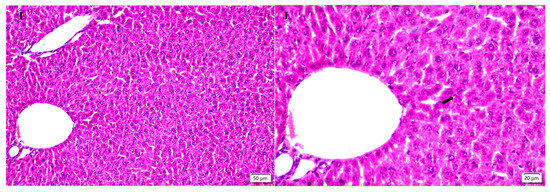

2.5. Hepatic Histopathological Changes

3.7. Hepatic Histopathological Changes